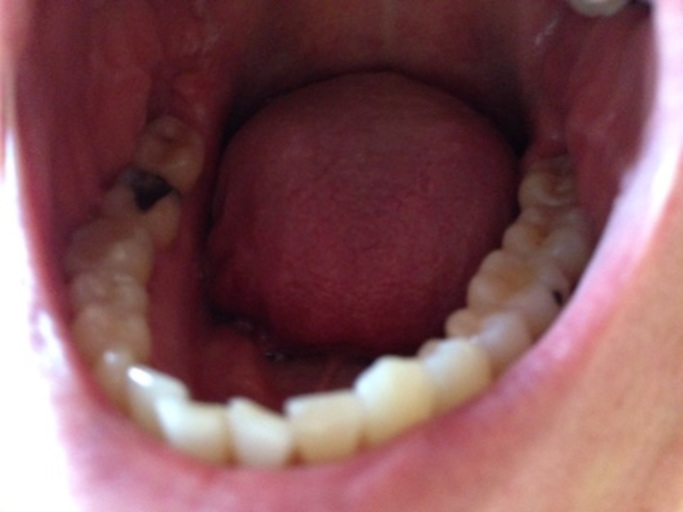

Hello, I have a question about my back molar on the bottom row. I have had white composite fillings as well as sealants in the past years ago. It appears I have a hole in my tooth and it looks as though the filling has broken leaving a nice sized hole on the surface. Is this possible or another cavity. Please help.

It is possible that if there was a filling placed in the tooth at one time, it could have broken.  However, many times the fillings deteriorate or come out due to recurrent caries.  Resin fillings need to be replaced with time, as do sealants.  If the  margin of the restoration begins to leak, it is possible for a new cavity to form around the restoration, weakening it.  This is not always the case, sometimes the restorations can crack and break.  Without a dental radiograph or picture it is hard to say for sure.  It is best to schedule an appointment with your dentist and have them restore the tooth back to full function.  If there was a restoration, it will be documented in your patient record.  Keep the area clean until you are able to see your dentist in order to risk further damage to the remaining restoration or tooth.

I believe you submitted your question twice, once without a picture. Looking at the picture, it appears as though there is recurrent decay around the restoration.  More than likely the restoration broke when the tooth structure underneath it became weak.  Schedule an appointment with your dentist to have the tooth evaluated.  If there is in fact decay under the restoration, you want to have it removed and the restoration replaced as soon as possible.  This will reduce the chances of a more extensive restoration as well as the decays proximity to the nerve of the tooth.